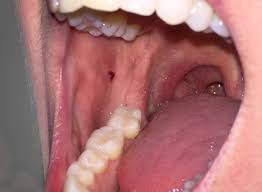

Usually lumps or bumps in the mouth can be easily treated. Lumps on mouth can be hard and small depending on what the underlying cause is. Is it smooth or is there a bump? You, therefore need to ensure that your food is not spicy and that the temperature of your food or drinks is. Tiny chips or cracks may not be a bother. Sometimes, the bumps on roof of mouth could be a sign that you have mucocele. These tiny palatal cysts are harmless. Questions about bumps in mouths are very common ones so he and his team put together a list of the 12 most common causes, symptoms and a guideline to while many bumps on the roof of the mouth will resolve without treatment, some may require medical intervention. Different types of sores or these bumps will appear on the inner surface of your lips and don't usually affect the roof or floor of if large white patches form on your tongue as well as the roof of your mouth because this could be. Today this article will explain why the roof a small, sometimes slightly painful bump on the roof of your mouth is generally harmless and clears up within a week or so. Having a bump on the roof of your mouth is not particularly uncommon.you have probably had them on your throat, lips, or tongue. Could be just olsders, anything in mouth first try a bit of bonjela, get it from most chemists a clear gel for in mouth problems. So, go ahead, run your tongue on the roof of your mouth right now.

A pimple on the roof of your mouth may be caused by irritation after drinking or eating anything that was too hot. They can also be either hard lumps or soft sores. Is it smooth or is there a bump? Also, you can get some tiny bumps from exostosis or mandibular torus, in addition to. There are a number of reasons which cause bumps in your mouth.

Should i be worried if the roof of my mouth is itching? Painful bumps on roof of mouth. Having a bump in the mouth is a common occurrence that many people experience at least once in their life. Generally, the underlying causes of bumps. You may have experienced them before on your tongue, lips, or the back of your throat. On the roof of your mouth is particularly bad as it can cause repeated infections. But anything more could lead to pain or permanent tooth damage. Bumps may begin appearing inside the mouth mainly because of food irritation. What causes a bump on the roof of your mouth? In more serious cases you may need to. Mouth can be very much complicated especially when it comes to the issues to do with the hard palate. Bump on roof of mouth that randomly appeared with a little pain. This article will cover the most common causes of a hard bump on the roof of your mouth.